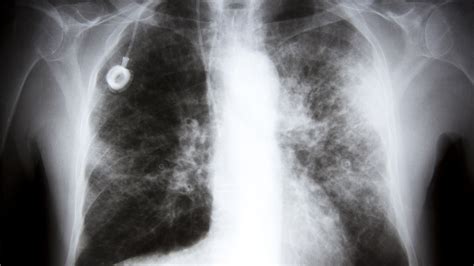

Diagnosing Lung Cancer Level 4 involves a comprehensive evaluation that includes:

• Imaging tests such as X-rays, CT scans, and PET scans